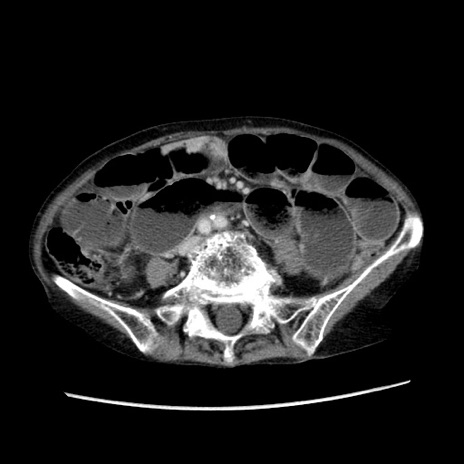

症例25(横断像)

【症例】80歳代女性

【主訴】胸のつかえ感

【現病歴】約9時間前に食後から胸のつかえた感じあり、嘔吐あり、来院。

【既往歴】胃癌(全摘)、胆摘、虫垂炎

【身体所見】心窩部に圧痛あり、反跳痛なし。

【データ】WBC 5700、CRP 0.05